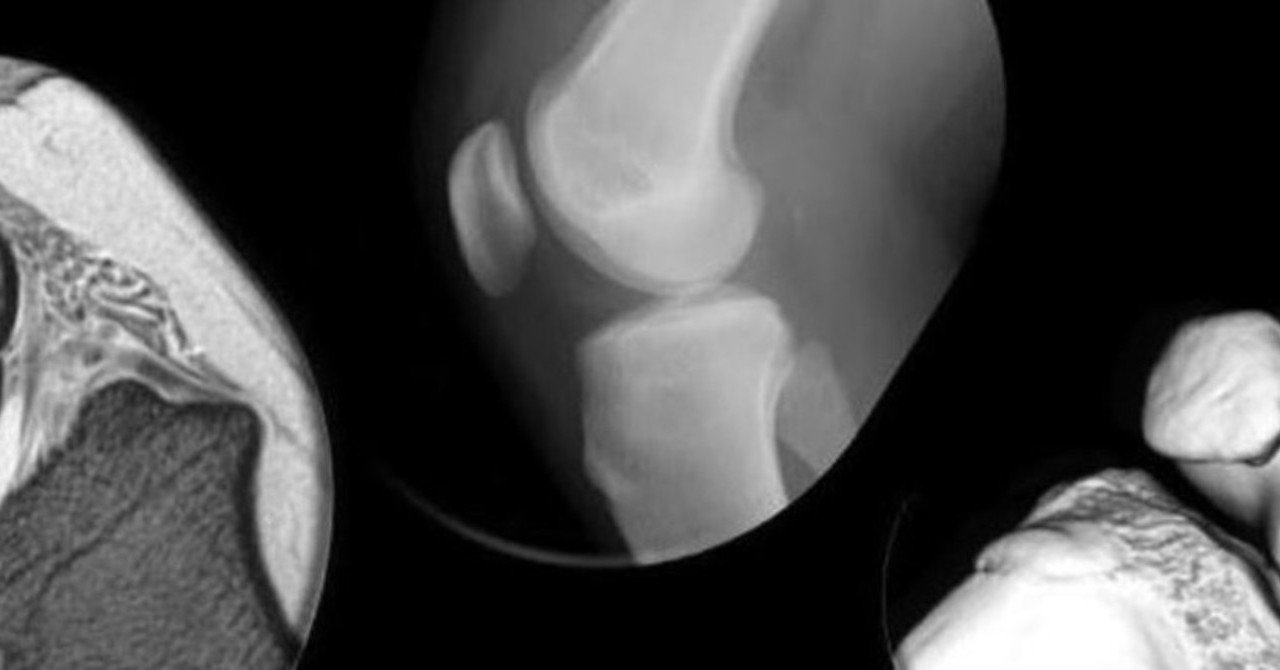

因について,半 月板の辺縁部に微少な出血の繰り返し, もしくは繰り返す外傷により半月板内部の変性をきた し,そ こに外方への力が加わることにより嚢腫を生じ るのではないかという仮説を述べて 05 半月板囊腫的手術是怎麼做的? 06 半月板囊腫關節鏡手術後如何康復? 01 什麼是半月板囊腫? 所謂囊腫,就是一包水而已。所以只要報告上說是囊腫,不管是肝囊腫,腎囊腫,膕窩囊C。病灶主要位於半月板前角邊緣和關節囊之間(箭頭) 半月板囊腫的 mri 典型表現為半月板外緣與關節囊之間出現的囊性病變,mri 訊號特點為 t1wi 呈稍低或低訊號,訊號均勻;t2wi 脂肪抑制呈高訊號